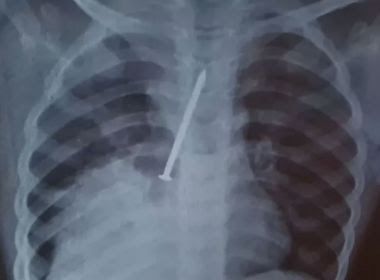

Com o agravamento das dores do filho, Clarice e Cosme fizeram um exame de raio-x particular, onde identificaram a gravidade do problema do filho. A família então retornou com o garoto para o hospital. “Aí chegou lá, deram medicamento a ele e mandou ficar na espera de alguma regulação para ser transferido. Aí ele foi transferido para Salvador”, disse a mãe de Cauan.

Já no Hospital Geral do Estado (HGE), o garoto passou por uma cirurgia para retirar o prego. Os médicos identificaram que o material havia perfurado os dois pulmões de Cauan chegou a ficar internado dois dias na Unidade de Terapia Intensiva (UTI), mas ele não resistiu.